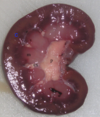

who does this kidney belong to?

cat